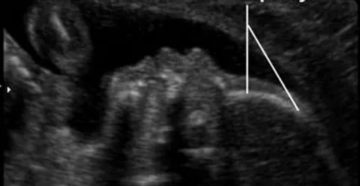

Расшифровка УЗИ малого таза у женщин Наверное, каждому посетителю кабинета УЗ-диагностики приходилось видеть на мониторе…